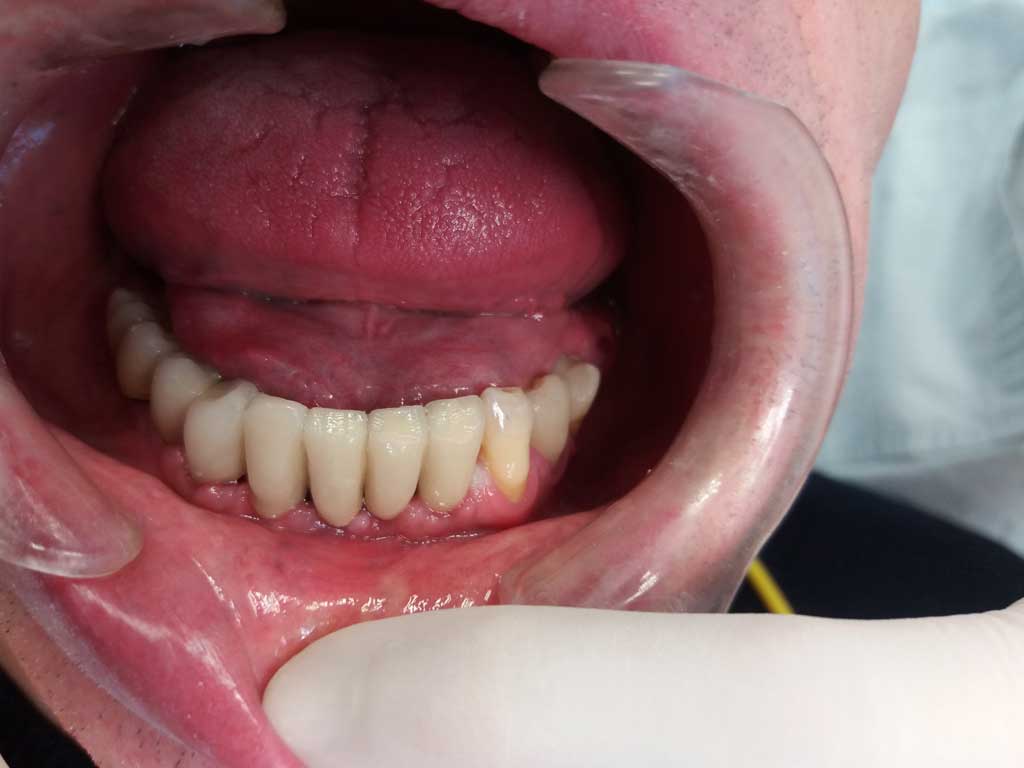

Il paziente è arrivato alla nostra attenzione con problemi gengivali ed elevata mobilità dei denti frontali inferiori, che li rendeva purtroppo non più recuperabili.

PRIMA